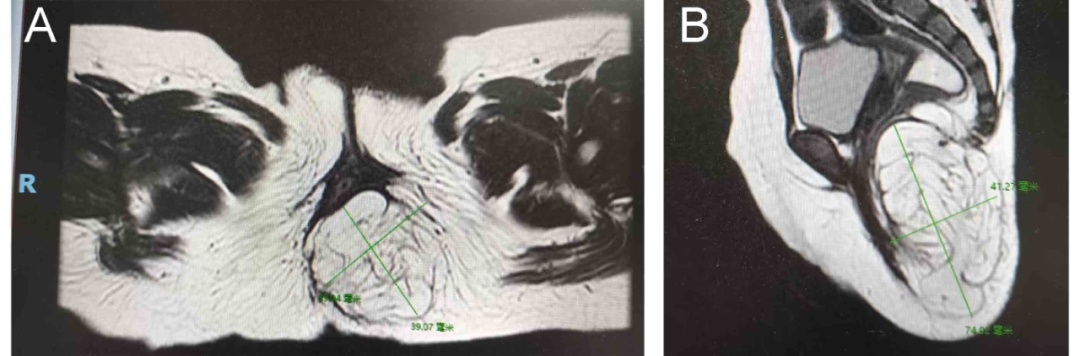

一家人觉得不对劲,随即带花花前往当地医院就诊,盆腔MR检查提示 “左臀部脂肪瘤”。“肿瘤”二字让家长慌了神,经打听,花花一家来到中山六院小儿外科,寻求进一步治疗。科室主任王德娟主任医师接诊,建议花花首先完善相关检查。

因为花花骶尾部肿物邻近直肠肛门和马尾神经及尾骨,伴随排便困难等临床症状,王德娟担心该肿瘤与腰椎神经有隐匿的关联,牵一发而动全身,若影响到腰椎将造成全身性的不良后果,严重者可能瘫痪。

谨慎考虑后,王德娟团队联合胃肠外科、麻醉科、儿科、放射诊断科、神经外科等专家,结合医院影像学检查结果,全面评估花花的病情,排除肿物与骶尾神经关联,决定采用经臀微创手术方式切除肿物。